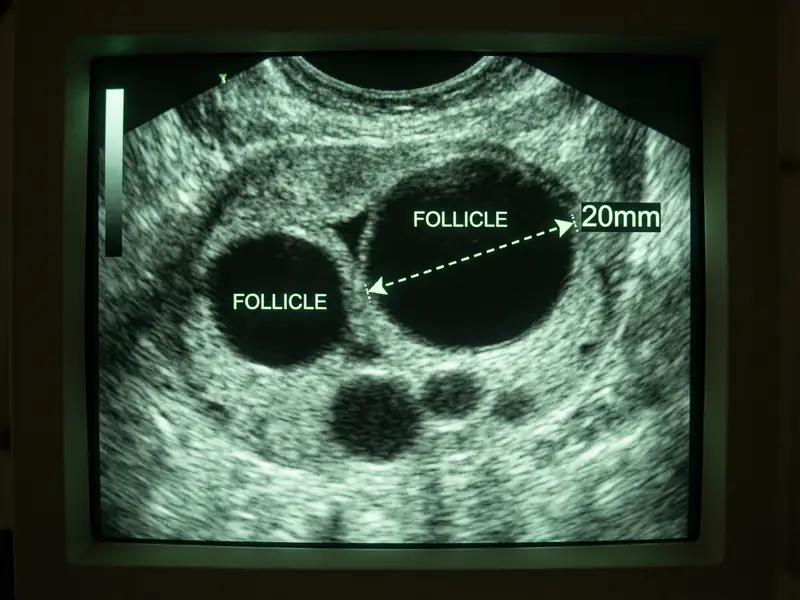

A follicle is a small fluid-filled sac inside the ovaries containing immature eggs. The size and number of the follicles is an indication of your fertility and vary between women.

For ovulation to occur, the follicle needs to reach approximately 18-24 mm.